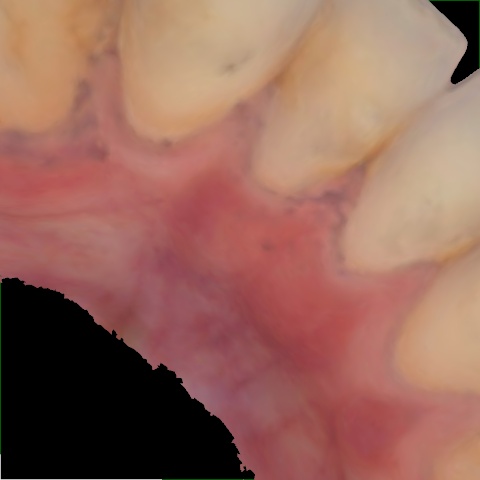

Annotated as "Bad"

Original Image Rendering Image